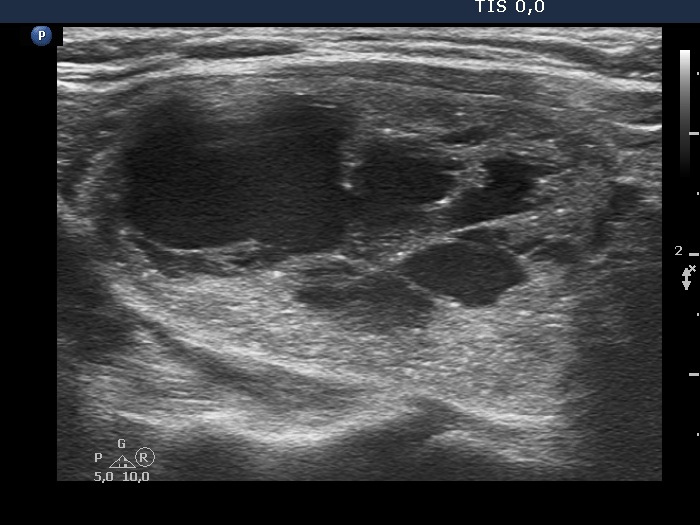

Ultrasonography. The thyroid was echonormal. There was a nodule presenting coarse calcification along its ventral surface. There was a spongiform-type cyst in the left lobe. The nodule has numerous echogenic figures most of them were caused clearly by posterior back wall enhancement.

Eight mL bloody cystic fluid was aspirated. After I aspirated 4 mL fluid, I have noticed that the cyst began to refill at once and a few minutes later the cyst became as large as before the aspiration.